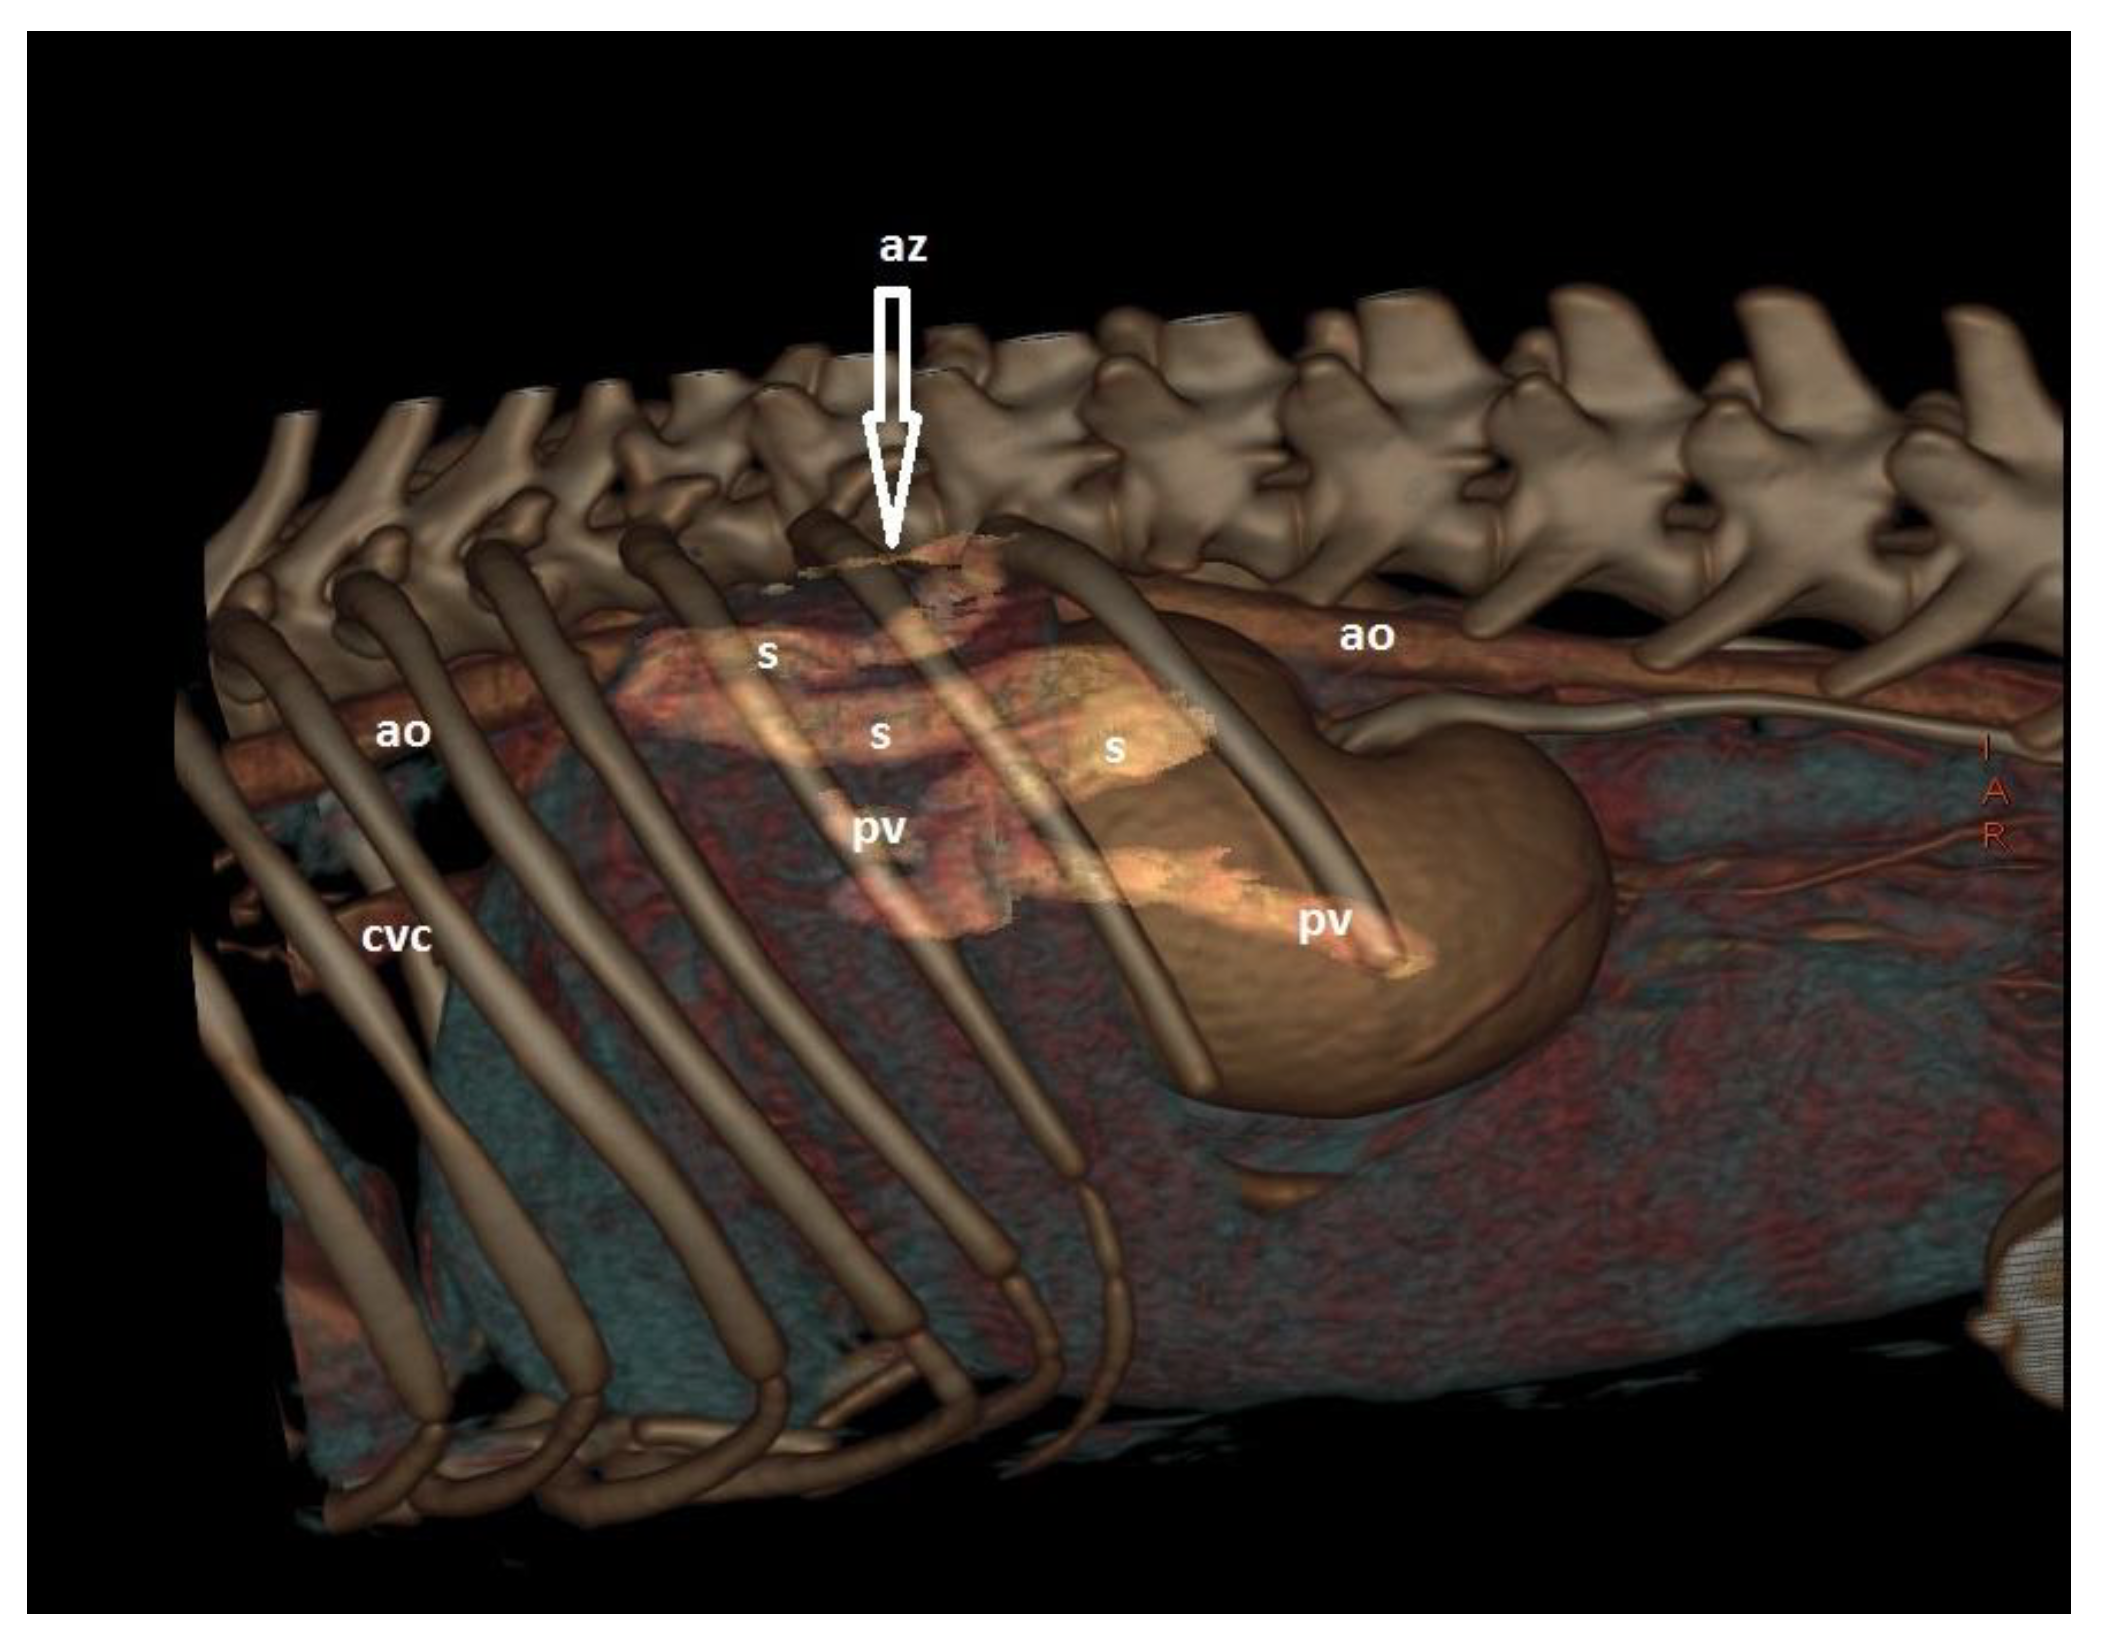

6. Clinical Signs/Physical Examination

9. Diagnostic Imaging